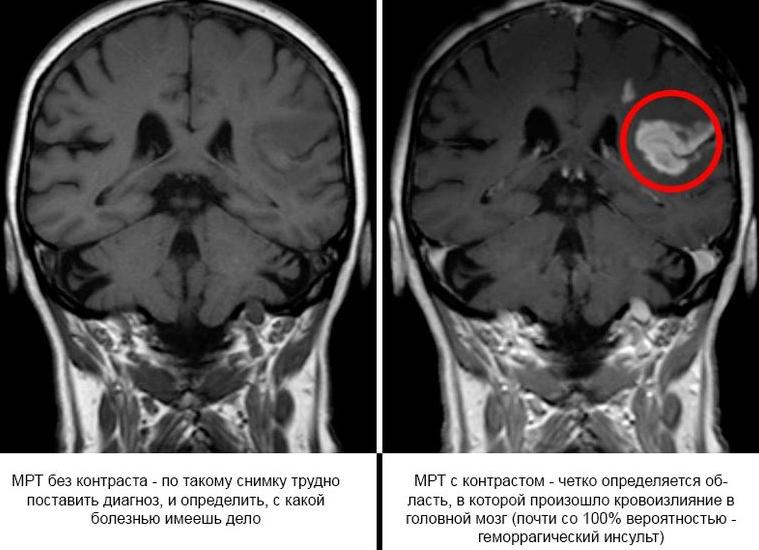

Использование контрастного вещества в ходе исследования позволяет сделать снимок более четким.

Поступая в кровь, гадолиний скапливается в тканях, благодаря чему слои, новообразования различной природы, становятся различимы очень четко.

С помощью обычной процедуры весьма успешно диагностируются многие патологии и отклонения, однако контрастирующее вещество способно проявить даже малейшие изменения в структуре головного мозга и сосудов, очаги заболевания, отследить развитие рецидива. С помощью контрастного МРТ можно проводить динамику изменений в организме после успешно проведенных сложных операций и отслеживать рост и структуру доброкачественного образования. В современной медицине это самое надежное, безопасное и информативное обследование, которое помогает спасать жизни людей и вселять веру в их полное выздоровление.